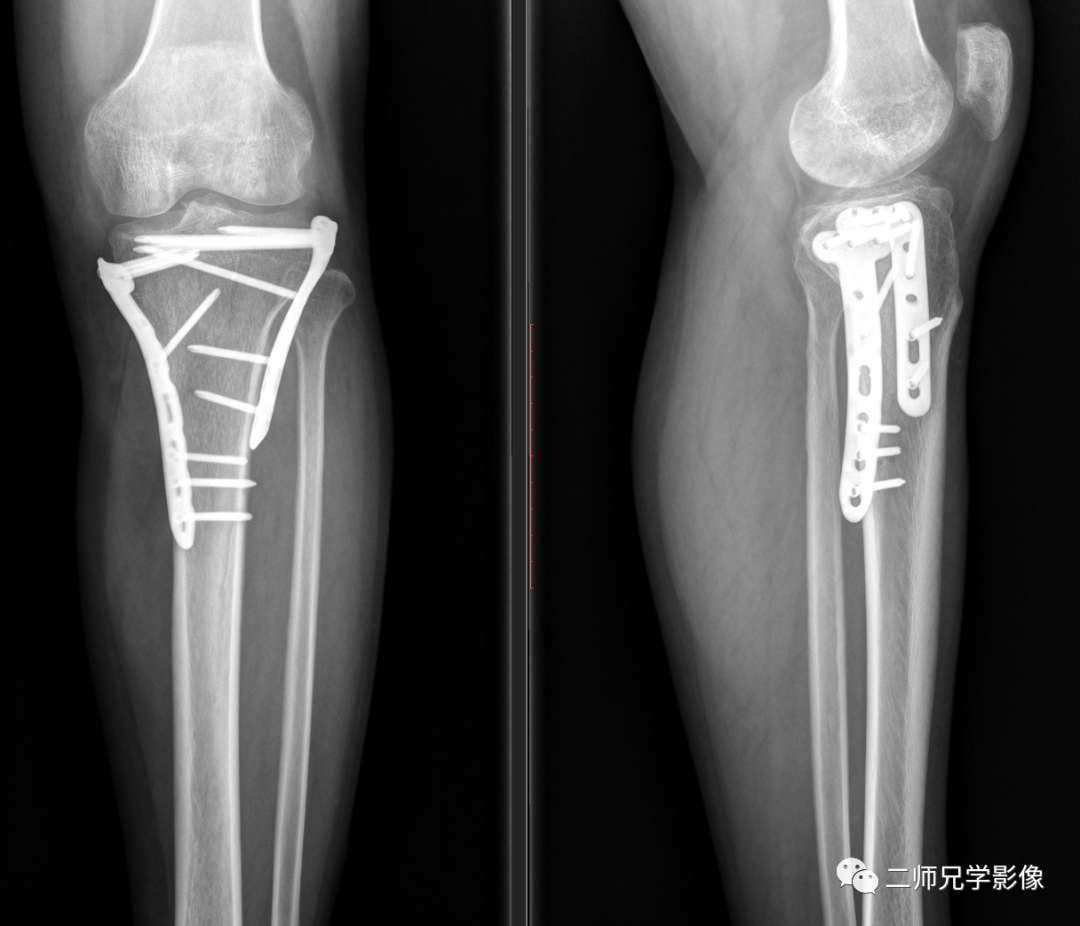

病例二:病人左胫骨平台骨折内固定复查,申请单:左胫腓骨正侧位(包膝)

左胫骨平台骨折内固定术后改变